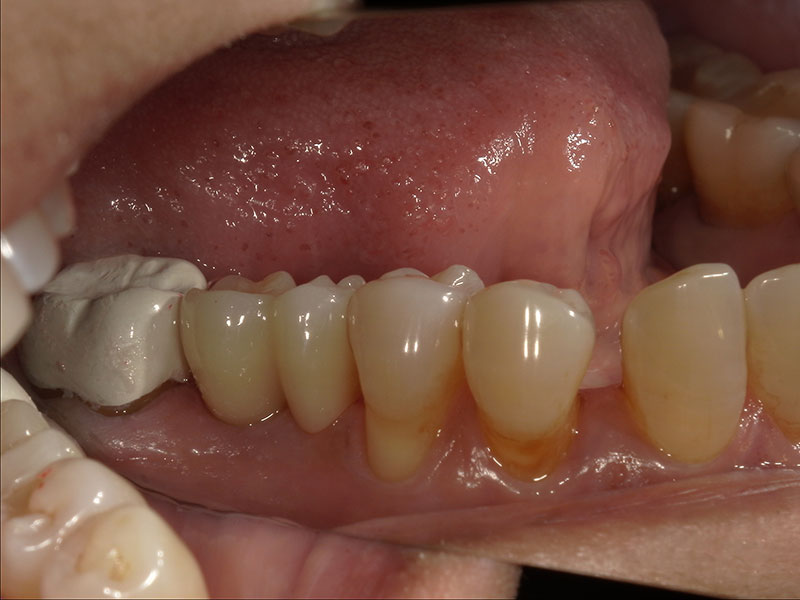

インプラント上部構造装着

インプラントの上部構造を装着しました。インプラント部の清掃性を考え、小臼歯が2つ並んだような形態にしました。こちらの形態の方が歯間ブラシが通しやすくインプラントが長持ちします。